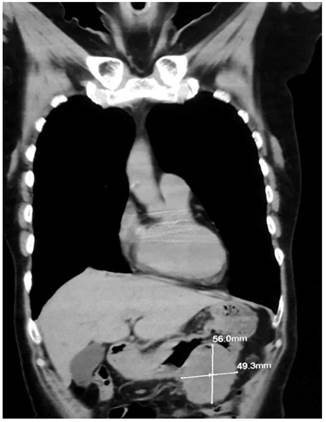

Initially, it was considered that the patient had an ulcerated GIST in the distal gastric body without active bleeding and further studies were carried out to evaluate local and regional involvement, including a computed tomography (CT) scan of the abdomen and pelvis where a gastrointestinal stromal mass located in the gastrocolic space and compatible with a GIST tumor (Figure 1) and a retroperitoneal mass or adenomegaly located behind the head of the pancreas (Figure 2) were found.

Figure 2 CT scan where the retroperitoneal mass or adenomegaly located behind the head of the pancreas can be observed.